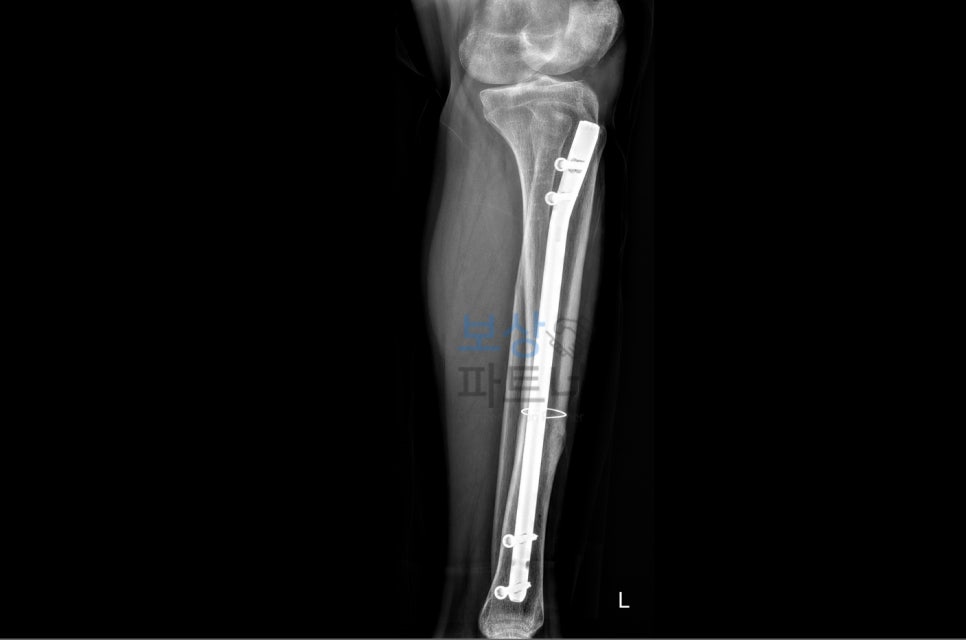

경골(tibia)은 정강이뼈로, 하퇴부에서 가장 큰 뼈이며 비골(fibula) 과 함께 다리를 지탱합니다. 이 부위가 골절되면 단순히 뼈만 부러지는 것이 아니라, 주변 혈관과 신경, 연부조직까지 손상될 위험이 높습니다.

특히 개방성 골절의 경우, 뼈가 피부 밖으로 노출되면서 감염 위험이 크게 증가하고, 골수염이나 불유합 같은 심각한 합병증으로 이어질 수 있는데요. 일반적으로 경골 골절 치료에는 체외 고정술, 관혈적 정복 및 금속 내고정술 같은 정형외과적 수술이 필요합니다.

또한 회복 과정에서도 장기간의 재활운동과 물리치료가 필수적이며, 제대로 된 치료가 이루어지지 않으면 하지 기능에 영구적인 장해가 남을 수 있습니다. 이처럼 경골 골절은 치료 비용도 많이 들고, 장기간 일을 못 하게 되며, 회복 후에도 후유증이 남는 경우가 많아서 산재 보상만으로는 실제 손해를 충분히 보전받기 어렵습니다.

60대 초반의 근로자께서 작업장 계단 사이로 발이 빠지면서 좌측 다리에 심각한 골절상을 입으셨습니다.

또한 경골의 개방성 골절과 비골 골절이 동반된 복합 손상임을 의학적으로 입증하고, 장기간의 치료 과정과 향후 예상되는 기능 장해를 종합적으로 평가하였습니다.